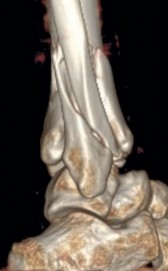

Fig 2.2-3a–h A CT scan with 3D reconstruction.

a–d Sagittal (a–b), coronal (c), and axial (d) images demonstrate displaced posterior, anterolateral, and medial fracture fragments resulting in intraarticular step and gap. The incongruent tibiotalar joint is best appreciated on the sagittal scan.

e–h The 3D reconstructed images show the external fracture anatomy and general alignment.